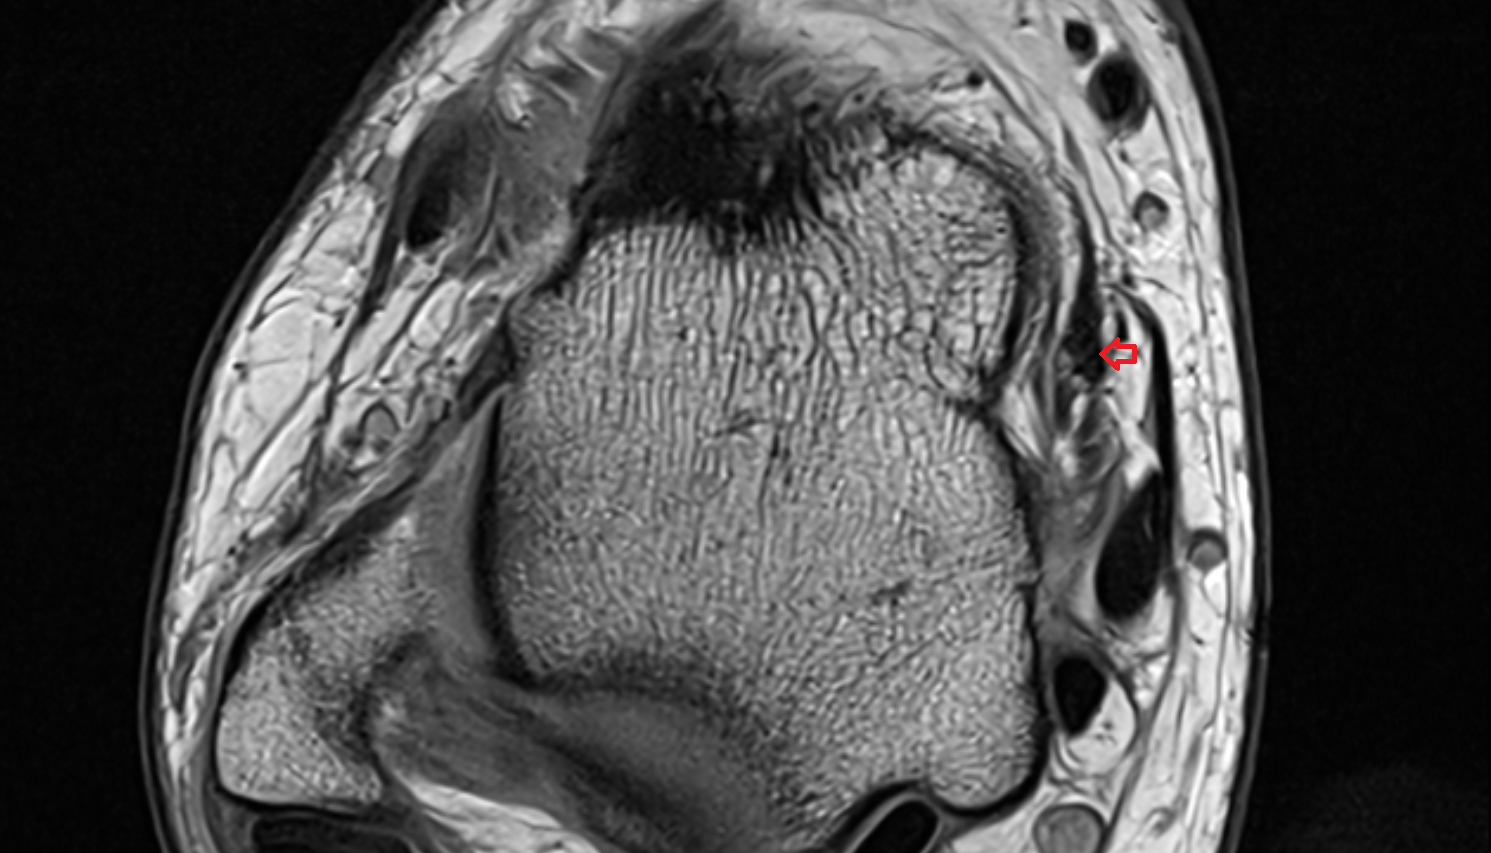

- Temporomandibular joint

- Mandibular condyle

- Mandibular fossa

- Lateral pterygoid muscle